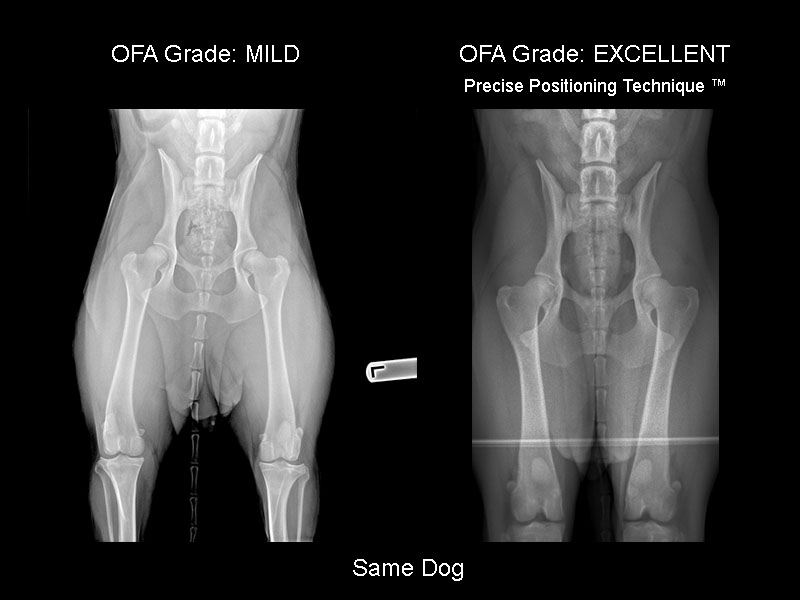

Precise Positioning Technique™ works!